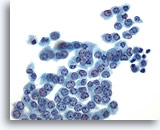

Figure 14

Peritoneal wash: Benign mesothelial cells in a cluster. 40X

Figure 14

Peritoneal wash:

Benign mesothelial cells in a cluster.

40X

Benign mesothelial cells from a peritoneal washing may also appear rounded up into a more three-dimensional group with some overlap. Close examination reveals uniform cells with benign nuclear features.